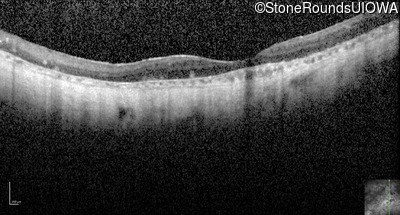

Optical Coherence Tomography - Right - No Light Perception

Exemplar / OCT Stack

Optical Coherence Tomography - Left - Light Perception